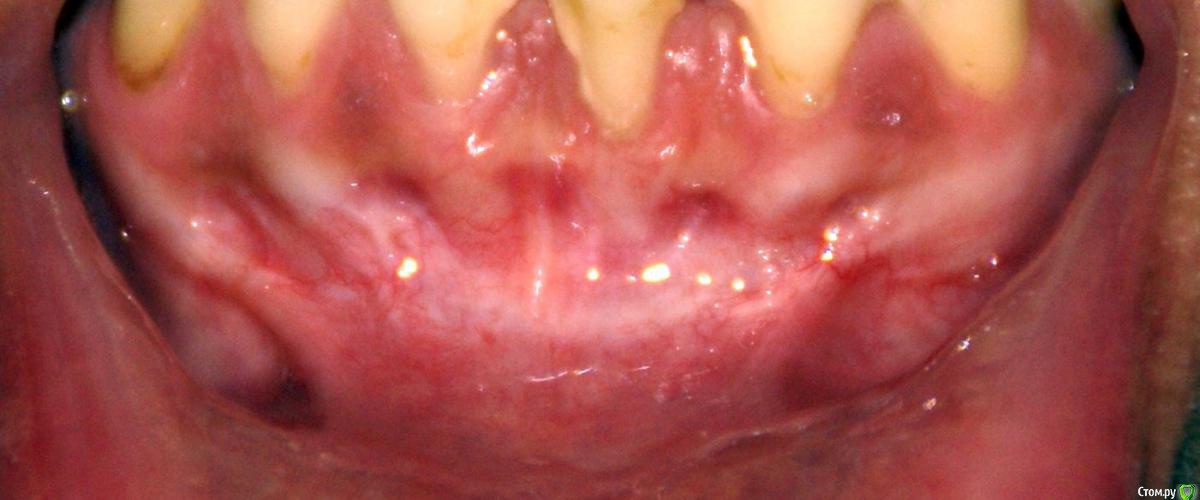

Irina_S Опубликовано 22 июня, 2017 Автор Поделиться Опубликовано 22 июня, 2017 Преддверие увеличилось достаточно.Как мне измерить это увеличение? Я не вижу разницы. Было:Стало:Вижу только отсутствие уздечки по центру. А по сторонам стало даже выше. И рубцы-тяжи влияют на дёсны около клыков. Ссылка на комментарий

Irina_S Опубликовано 25 июня, 2017 Автор Поделиться Опубликовано 25 июня, 2017 Доброго дня всем специалистам, заглянувшим сюда! Извините, если задаю некоторые вопросы, ответы на которые не находятся в вашей компетенции. Мне это сложно определить, потому что подсознательно врач же должен знать больше, чем пациент.Но вот ответ на мой, возможно, последний в этой теме вопрос, наверняка знают многие хирурги. Я прочитала в учебнике для стоматологов описание операции вестибулопластики, и там описывается разрез от зуба 35 до зуба 45. А мне, насколько я видела при заживлении, да и сейчас на фото видно по рубцам, делали меньшей длины - от клыка до клыка. Так вот, было бы у меня меньше неприятных послеоперационных ощущений и меньше тяжей, если бы операция была сделана в точности по книжке? Может, всё дело в отклонении от стандартных правил? Ссылка на комментарий

Irina_S Опубликовано 26 июня, 2017 Автор Поделиться Опубликовано 26 июня, 2017 Спасибо всем за ответы! Рана меньше - это, с одной стороны, хорошо, конечно. Но мне кажется, что именно из-за уменьшения длины разреза возникла чрезмерная натянутость, которой не было до операции. И когда я массирую давящими движениями вниз, то вижу, как натягиваются и белеют рубцы и оттягивают дёсны почти под всеми зубами. На сегодняшний день заметно опускание дёсен по сравнению с ситуацией до операции. Получается, что действиями, которые должны мне помочь в восстановлении, я только делаю хуже? Возможно ли восстановление дёсен, когда пройдёт тот самый неясный по продолжительности период заживления, когда тяжи перестанут тянуть? Как мне правильно поступить, чтобы не ухудшать ситуацию дальше? Если надо всё переделывать, то я готова к этому. Ссылка на комментарий

Bier Опубликовано 26 июня, 2017 Поделиться Опубликовано 26 июня, 2017 нужно наладить гигиену прежде всего, у вас все в камнях и налете. 2 Ссылка на комментарий